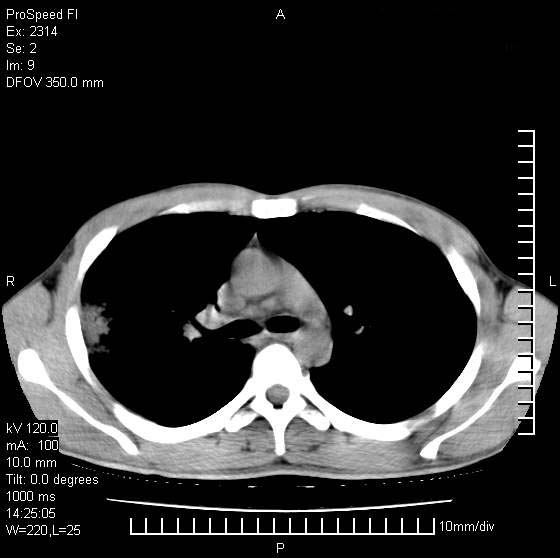

男性,再生障碍性贫血,入院前发热10天,最高40c,右侧胸痛,外院ct示右上,中肺边缘模糊的球性影(就是我现在图中标示的范围),考虑炎症,在我院使用头孢呋辛,洛美沙星10天,高烧消退,自感下午稍有发热,但今天ct示右上,中肺病灶明显扩大,还是考虑炎症,看其中的球型影是否霉菌感染??,是否能排除结核?

肺脓肿,伴双肺播散

支持考虑真菌感染,内部密度低些,且与外壁有分离,不符合肺脓肿表现,但最好有前片对比,